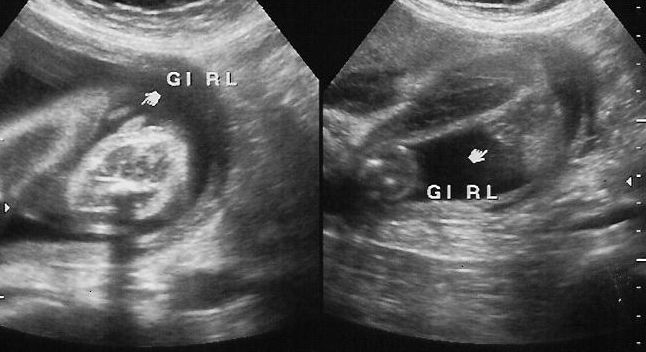

An ultrasound technician drives imaging equipment such as sonography and ultrasound diagnostic images to take pictures, document, and verify digital images of patient's tissues, internal organs, and blood flow so doctors can diagnose successfully and correctly illnesses and diseases.... How to Become an Ultrasound Technician in 5 Steps. Explore the career requirements for ultrasound technicians. Get the facts about certification, degree requirements, job outlook and salary to determine if this is the right career for you.